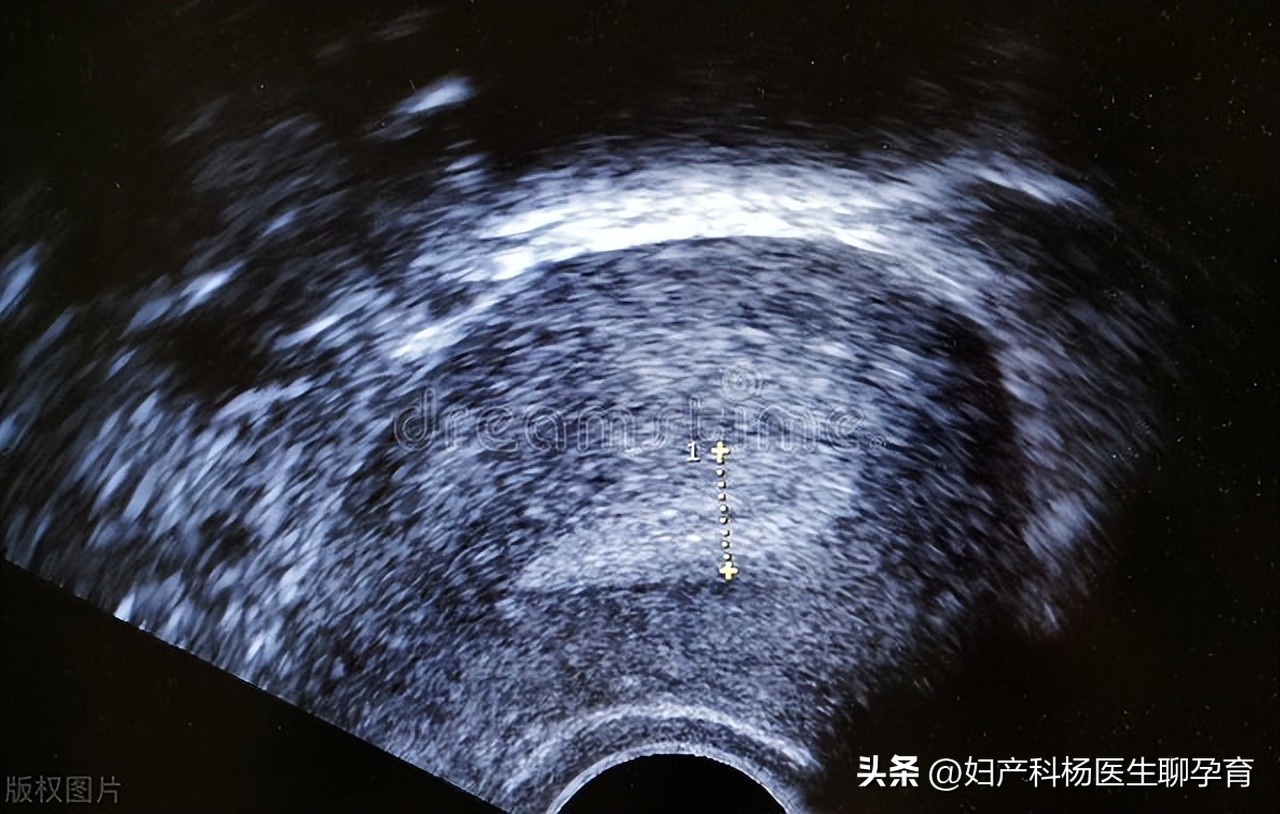

子宫内膜的作用是什么?在不同阶段,正常的子宫内膜是多厚?

女性子宫内膜就像是土壤,孕卵就像是发芽的种子,营养达不到,就可能会枯萎。如果子宫内膜薄,怀孕之后可能会发生流产。

一般来说子宫内膜正常的厚度是8-10毫米。

子宫内膜的变化:

月经期,子宫内膜功能层脱落保留基底层;增生期,月经第6-14天内膜厚达1-3毫米;分泌期,月经第15-28天,子宫内膜厚达5-7毫米。